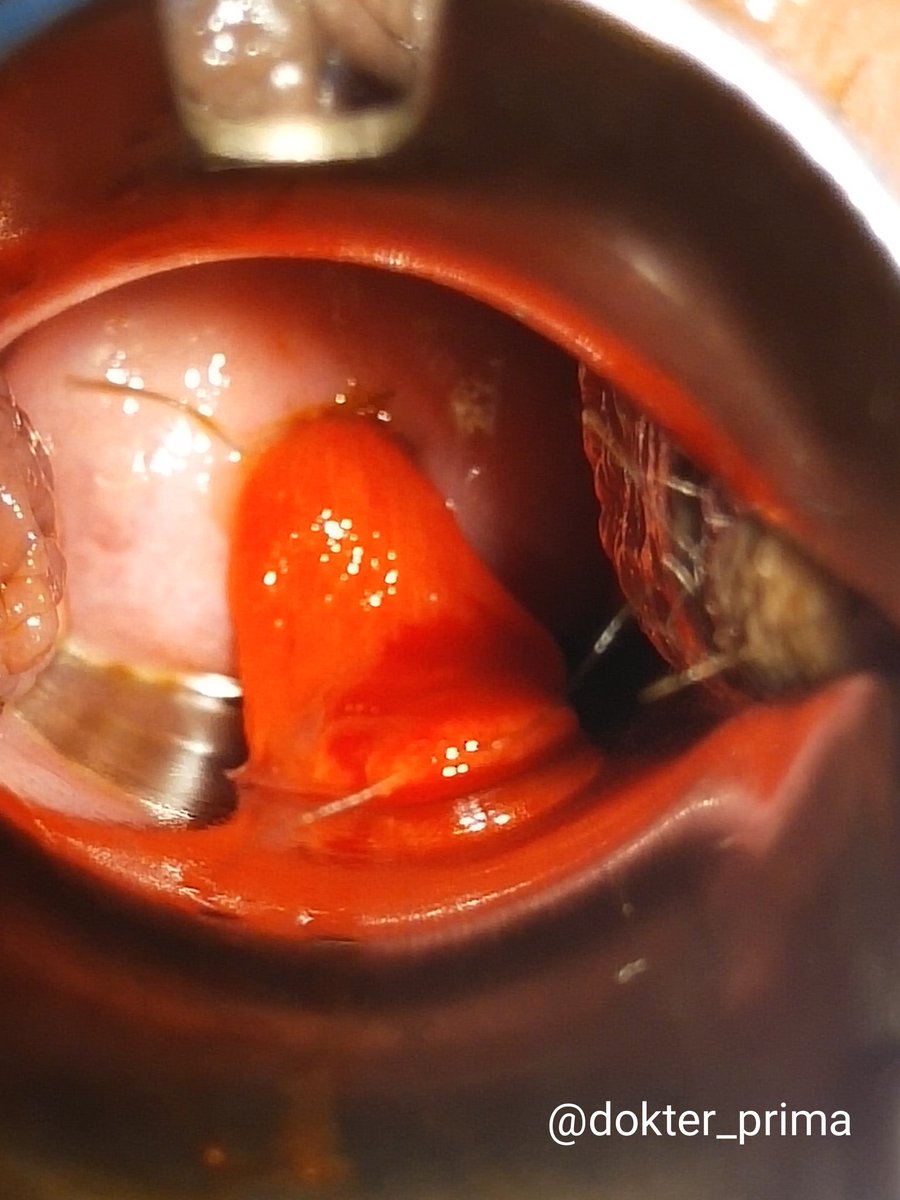

Tapi penting sekali untuk PERIKSA DALAM. Lihat serviks nya untuk cari sumber perdarahan. Jika normal baru USG baik-baik untuk cari sumber dari rahim atau indung telur/hormonal.

#polipserviks #tumorrahim #poliprahim